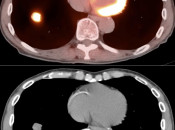

Pulmonary Nodules:

Assessment of a pulmonary nodule involves comparison of its metabolic activity to either background lung uptake (meaning that any uptake in a lung nodule is worrisome) or to mediastinal blood pool uptake. Assessment of pulmonary nodules is addressed in detail, here.